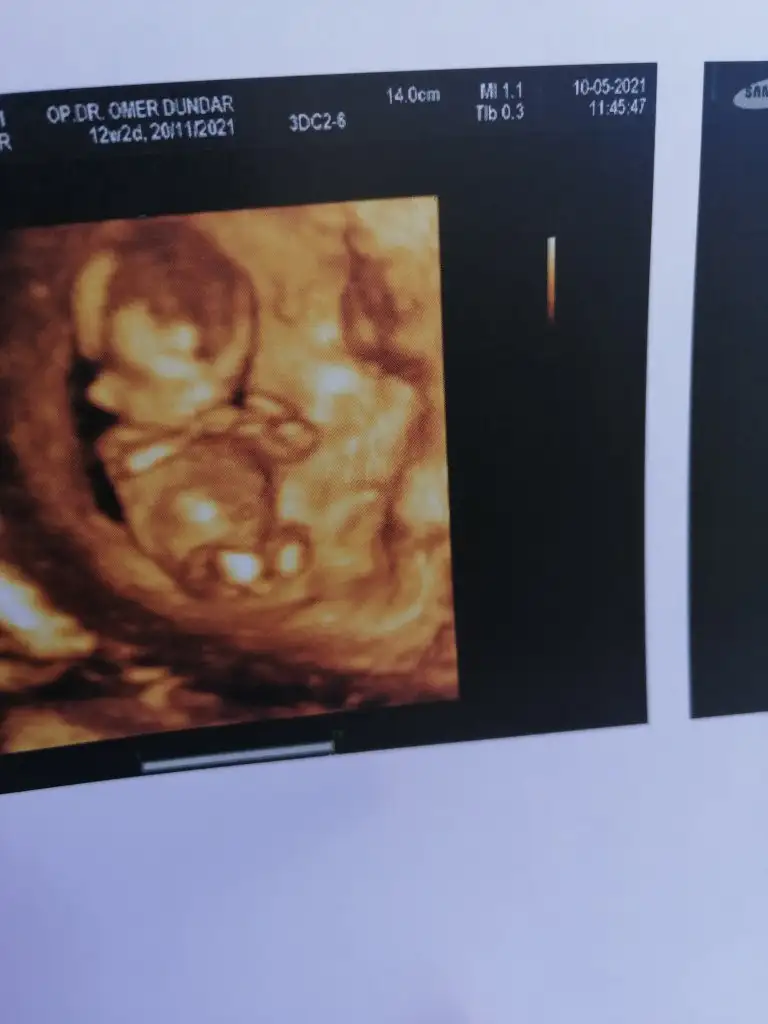

Maşallah allah sağlıkla kucağınıza almayı nasip etsinBide 4 boyutlusu var

Yaaa yerimm maşallah ❤Bide 4 boyutlusu var